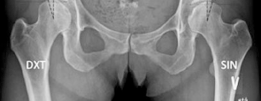

Key radiographic parameters are critical in quantifying the degree and pattern of dysplasia. These include the lateral center-edge angle of Wiberg (normal >25 degrees), the anterior center-edge angle of Lequesne (normal >20 degrees), the Tönnis angle or acetabular index (normal <10 degrees), and the femoral epiphyseal acetabular roof index.

Symptomatic presentation typically involves activity-related groin pain, mechanical symptoms such as catching or clicking (indicative of concomitant labral pathology), and fatigue in the hip abductors. Radiographically, a lateral center-edge angle of less than 20 degrees, an anterior center-edge angle of less than 20 degrees, and an elevated Tönnis angle confirm the diagnosis.

Standard radiographic evaluation includes an anteroposterior pelvis radiograph, a false profile view of Lequesne, and a Dunn lateral or cross-table lateral view. The AP pelvis allows for the measurement of the LCE angle, Tönnis angle, extrusion index, and evaluation of the Shenton line. The false profile view is critical for assessing anterior femoral head coverage (ACE angle) and evaluating the anterior joint space.